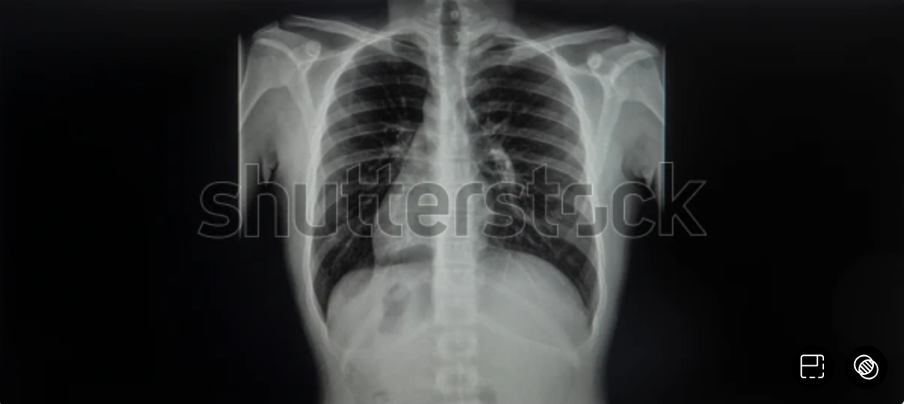

Trái tim là cơ quan quan trọng nhất trong cơ thể, đảm nhận vai trò bơm máu giàu oxy và dinh dưỡng đến nuôi các cơ quan, tế bào trong cơ thể. Bản thân trái tim cũng có 1 hệ thống mạch máu nuôi các tế bào cơ tim được gọi là hệ mạch vành. […]